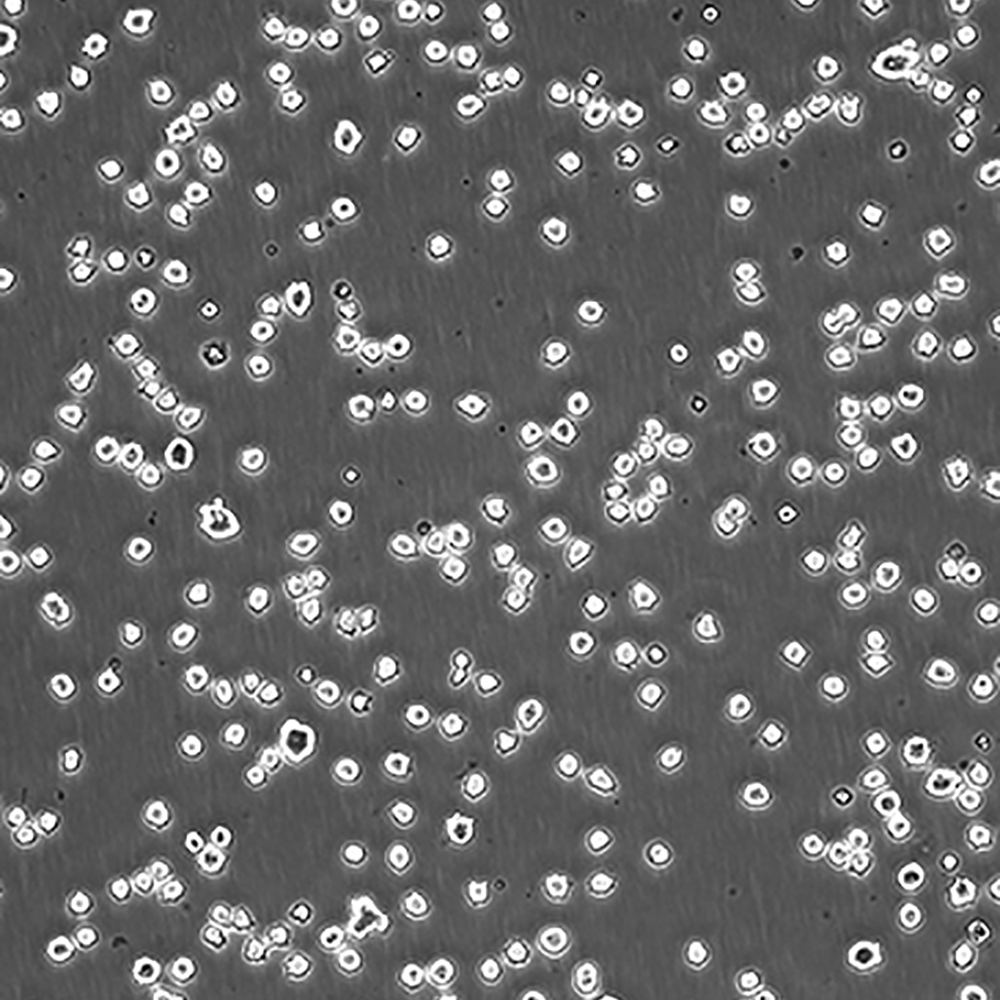

產品名稱 DB

中文名稱 人彌漫性大B細胞淋巴瘤細胞

組織來源 彌漫性大B細胞淋巴瘤;男性

生長特性 懸浮

培養基 DMEM90%;FBS10%;1%雙抗。

傳代方法 Maintain cultures at a cell concentraion between between 1 X 10(5) and 1 X 10(6) viable cells/ml.

培養條件 Atmosphere: Air, 95%; CO2, 5%。Temperature: 37℃